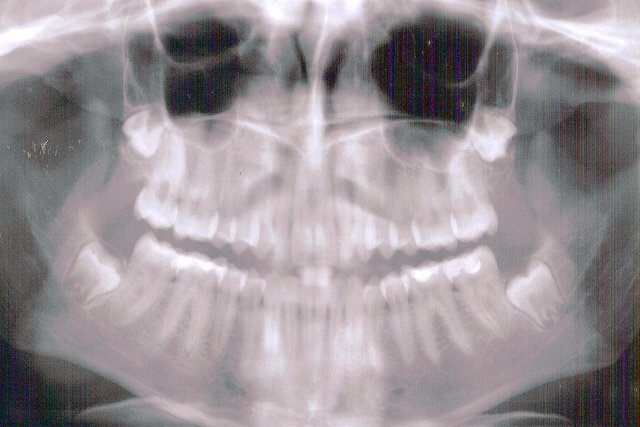

“Through the DBPs, we will be able to concentrate more on preventive care for the younger SoonerCare population,” OHCA dental director Dr. Karen Luce said in the press release. “Currently, the SoonerCare population under age 21 [is not regularly] utilizing the preventive care benefit. They tend to not be treated until there’s pain and need severe work. DBPs will incentivize members to have consistent appointments and have their teeth cleaned every six months. This change will prevent a good deal of restorative care and improve overall oral health.”

OHCA senior media relations professional Katelynn Burns said the agency’s most recent data about SoonerCare dental benefit usage show that, for Fiscal Year 2018, about 49 percent of children ages 3 to 20 had at least one preventive visit. About 16 percent of 1 and 2 year olds had a preventive visit.